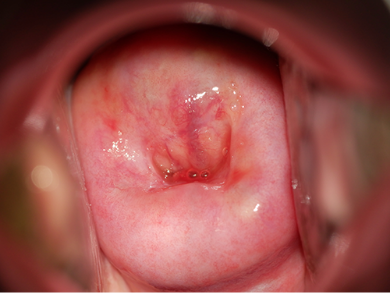

グリーン光

緑色のライトを当てることで、血管所見が観察しやすくなります。(±3段階調整可能 写真は±0)